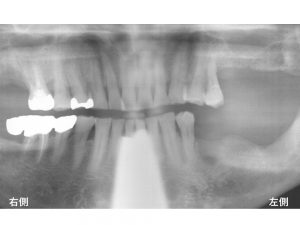

重度歯周病でした。

以下は初診のレントゲンです。

上顎前歯部の4歯は保存することができませんでしたので抜歯と診断しました。

抜歯後には、インプラント治療をご希望されましたので

4歯欠損に対して2本のインプラントを埋入し、

4歯分の被せ物を作成するインプラントブリッジとしました。